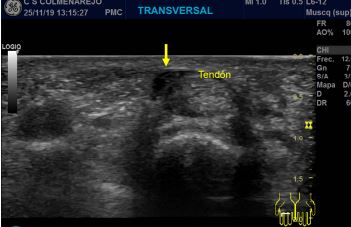

Hallazgos ecográficos

Se visualiza engrosamiento hipoecoico difuso en polea A1, líquido en las inmediaciones del tendón y tendón tumefacto.